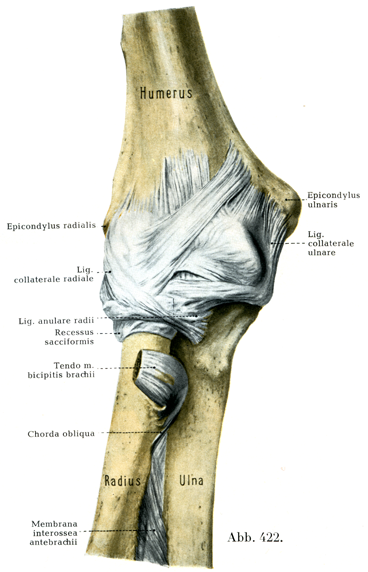

[図421, 422]右の肘関節(4/5) 図421は上腕骨滑車の軸に垂直な面で切断し,その外側半を内側からみたところ.図422は肘関節を前方からみたところ.

関節包は肘関節としてひとまとまりをなす3つの関節に共通であって,掌側では背側よりも強い.関節包は中くらいの屈曲位のときは,掌側でも背側でもゆるんでいる.完全な屈曲のときには関節包の背側半が緊張し,完全な伸展のときには掌側半が緊張する.橈骨輪状靱帯より下方へ関節包が伸びだしている部分は嚢状陥凹Recessus sacciformisとよばれる.

関節包は掌側では上腕骨の烏口窩と橈骨窩との上方1/2 mmのところから起り,尺側および橈側上顆は関節包の外に取り残されている.そのさい滑車の内側縁に沿って約2mmの距離をおいて付着し,また小頭の外側および背側の軟骨縁にはそのすぐきわに付き,背側では肘頭窩の中央に付着している.尺骨においても軟骨縁に沿って付着するが,肘頭と烏口突起のところでは軟骨縁からさらに多少はなれたところに付いている.橈骨では上端から約15mm下方で頚に付着しており,この部分は関節包が繊細でうすく,また橈骨輪状靱帯の下方には上述の嚢状陥凹をつくっている.

特別の装置としては3つの補強靱帯があるただしこれは関節包および焼側側副靱帯と結合して分離できない橈骨輪状靱帯Lig. anulare radiiをもいっしょに算えてのことである.他の2つの補強靱帯が尺側および橈側側副靱帯である.尺側側副靱帯Lig. collaterale ulnareは上腕骨の尺側上顆から起って,その線維は扇状に尺骨に向って放散している.

橈側側副靱帯Lig. collaterale radialeは橈側上顆の掌側面および下面から起って,2つのたがいに離開する束に分れ,橈骨小頭の掌側および背側をへて,尺骨の橈骨切痕の掌側縁と背側縁にいたる.この靱帯は続骨輪状靱帯の輪走線維ならびに前腕の表層の伸筋の起始腱と密に癒合している.橈骨輪状靱帯については前述の肘関節の続尺部の項(289頁)を見られたい.

関節包の掌側面の上には比較的弱い補強線維束が縦・横・斜めに走っている.そのうち斜めの1線維束がつよく発達しているのが普通で(図422),これは尺側上顆のあたりから起って輪状靱帯に達している.同様に後面にも縦の方向に走る散在性の線維束がある(図428).